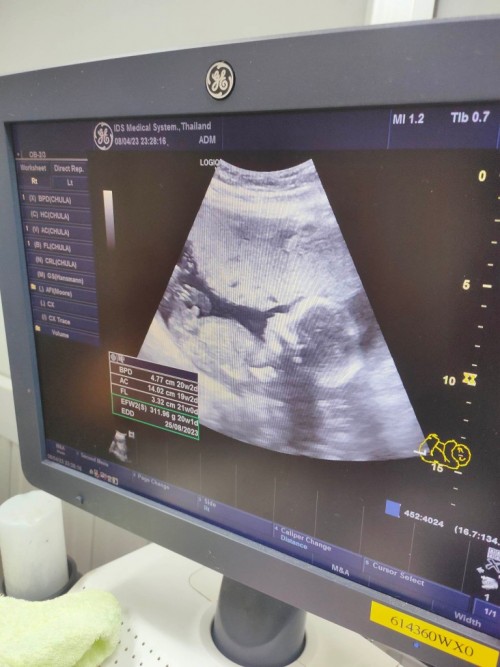

เอาภาพอัลตราซาวด์มาอวดจ้า บ้านนี้แลบลิ้นให้ป้าหมอไป1ที แถมเตะโชว์ไป1ที5555ป้าหมอบอกอาจจะดื้อนะ #ลูกสาว #ท้องแรก